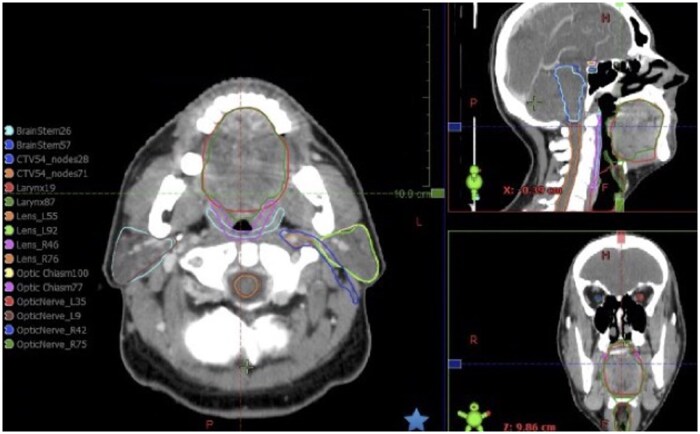

目的:根据NICE指南的要求,综合评估ART-Plan™(使用人工智能(AI)的自动轮廓软件)在现实环境中轮廓头颈癌(HNC)放疗结构(高危器官和可选淋巴结体积)的能力。方法:回顾性评价(n = 60)比较临床使用的轮廓与人工智能轮廓,采用体积骰子相似系数(VDSC)和盲法放射肿瘤学家(RO)轮廓偏好评估。然后对HNC放疗患者(n = 61)前瞻性地生成ai轮廓,然后进行ROs复查。ro记录定性评分和评审/编辑时间。人工智能轮廓线与最终轮廓线进行几何和剂量学比较。计算各指标之间的相关系数。结果:不同结构的回顾性中位VDSC差异很大(0.23-0.88)。31.4%的盲法轮廓评估者更喜欢临床医生生成的轮廓,32.9%的人更喜欢人工智能生成的轮廓,35.7%的人没有显著差异。前瞻性评估表明,与手动轮廓相比,人工智能轮廓在审查/编辑所有结构时节省了大量时间。定性评分显示大多数结构的中位数评分≥4(表明不需要编辑)。除喉部外,其余部位的几何特征均具有较高的相似性。剂量学评估显示喉和选择性淋巴结体积的临床显著剂量差异。定性评分与所有几何指标之间存在很强的相关性。结论:人工智能轮廓具有良好的定性性能,有利于节省时间。商业人工智能解决方案和实施中心之间存在协议差异。正在进行的人工智能轮廓的最终临床医生审查仍然至关重要。知识的进步:这是第一个证明ART-Plan™在现实工作流程设置中具有卓越定性评级和显著节省HNC放疗轮廓时间的能力的研究。5分李克特量表定性评分与几何指标密切相关。

Objectives: To comprehensively evaluate the ability of ART-Plan (autocontouring software using artificial intelligence [AI]) to contour head and neck cancer (HNC) radiotherapy structures (organs-at-risk and elective nodal volumes) in a real-world setting, as required by NICE guidelines.

Methods: Retrospective evaluation (n = 60) compared clinically used contours to AI-contours, using volumetric dice similarity coefficient (VDSC) and blinded radiation oncologist (RO) contour preference assessment. AI-contours were then generated prospectively for HNC radiotherapy patients (n = 61), before review by ROs. ROs recorded qualitative scoring and review/editing time. Geometric and dosimetric comparison of AI-contours and final contours was undertaken. Correlation coefficients between all metrics were calculated.

Results: Retrospective median VDSC varied widely for different structures (0.23-0.88). 31.4% blinded contour assessments preferred clinician-generated contours, 32.9% preferred AI-generated contours, 35.7% saw no significant difference. Prospective evaluation showed AI-contour yielded significant time-saving in reviewing/editing for all structures compared to manual contouring. Qualitative scores demonstrated most structures had median scoring ≥4 (indicating no editing required). Geometric metrics showed high similarity for all structures except larynx. Dosimetric evaluation demonstrated clinically significant dose differences for larynx and elective nodal volumes. Strong correlation was seen between qualitative scoring and all geometric metrics.

Conclusions: AI-contours showed excellent qualitative performance and facilitated time-saving. Protocol differences exist between commercial AI-solutions and implementing centres. Ongoing final clinician review of AI-contours remains essential.

Advances in knowledge: This is the first study demonstrating ART-Plan's capability for excellent qualitative ratings and significant time-savings for HNC radiotherapy contouring in a real-world workflow setting. 5-point Likert-scale qualitative scoring correlates strongly with geometric metrics.